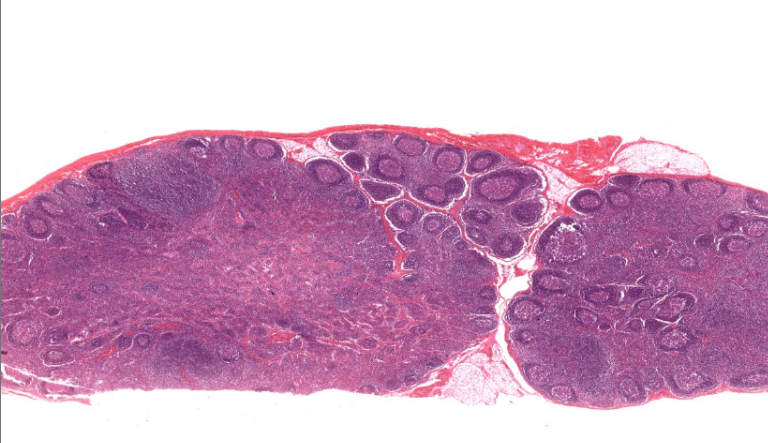

tonsil

pat of lymph system

produces WBCs

(tissue type)

stratified squamous epi

shown on the tonsil

lymph nodules

aggregation of lymphocytes that have germinal centers

crypts of tonsils

where the food and such enters/is tested